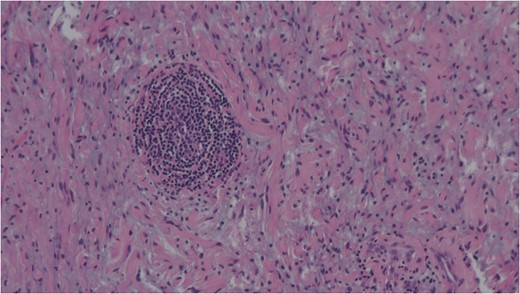

Spindle cells set in a myxoid stroma characteristic of schwannoma. Haemotoxylin and eosin (H&E).

FNAC remains a valuable tool to characterize neck masses but its accuracy in schwannoma is only reported to be 20–25% [4, 6]. Macroscopically, schwannomas are smooth and uniform and often attached to their nerve of origin which may help intra-operative diagnosis. Histologically, schwannomas are encapsulated and consist of alternating Antoni-A and Antoni-B regions [7]. Ancient schwannomas can be recognized by their additional degenerative features such as fibrosis, cystic necrosis and degenerative nuclei [7]. They can often be mistaken for malignant tumours due to nuclear atypia and hyperchromasia [7].